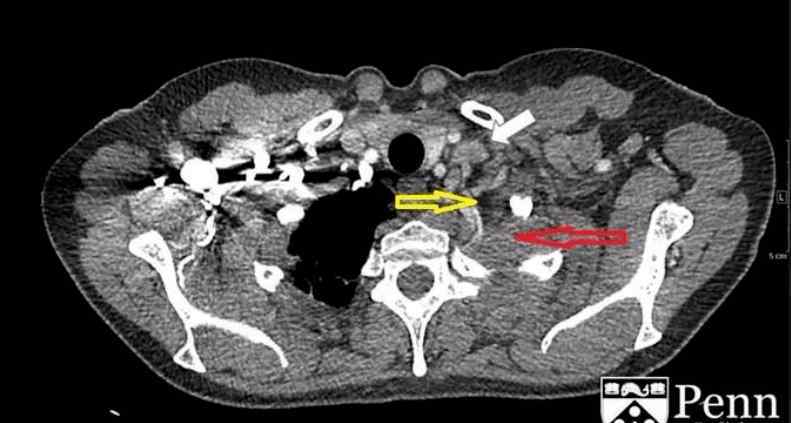

图2显示增强CT的纵隔窗。左肺尖可见分叶状肿块(红色箭头),中央可见坏死区(黄色箭头),与邻近胸膜分界不清,左侧锁骨可见肿大淋巴结(白色箭头)

胸部CT显示左肺尖是一个具有分叶和中央坏死区的占位性病变,与邻近胸膜无法区分,大小约为4.7×4.9×3.2cm,无明显骨转移征象。左侧锁骨上和左侧肺门上淋巴结肿大。

CT:平片CT可以用来确认平片上的高密度影。此外,它还可以用于评估骨骼受累。平片对肺、胸膜、胸壁和上腹部肿瘤转移的诊断价值有限。增强CT对评估血管受累和淋巴结受累非常有用。

图2显示增强CT的纵隔窗。左肺尖可见分叶状肿块(红色箭头),中央可见坏死区(黄色箭头),与邻近胸膜分界不清,左侧锁骨可见肿大淋巴结(白色箭头)

胸部CT显示左肺尖是一个具有分叶和中央坏死区的占位性病变,与邻近胸膜无法区分,大小约为4.7×4.9×3.2cm,无明显骨转移征象。左侧锁骨上和左侧肺门上淋巴结肿大。